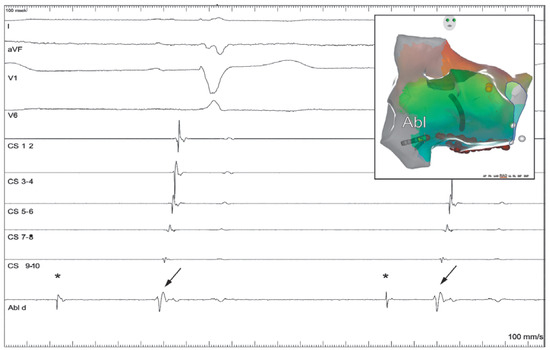

Dual Tachycardia Involving the Cavotricuspid Isthmus and Eustachian Ridge

Case report